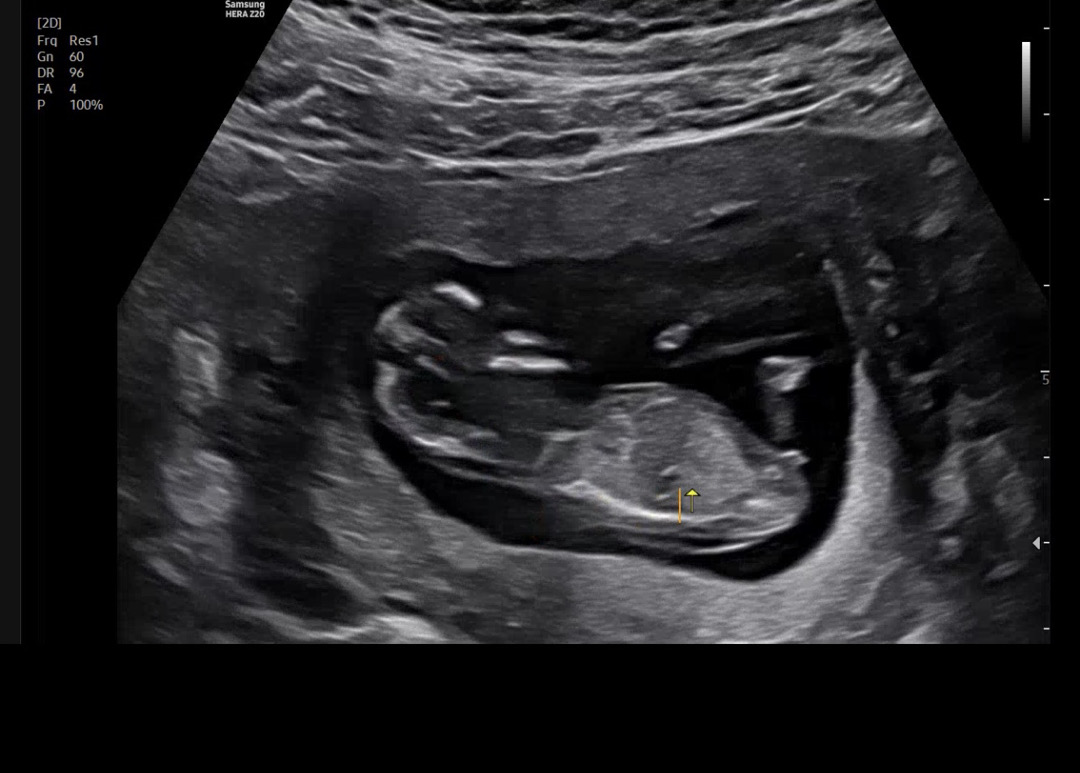

오늘날짜로13주차 각도법 고수선생님들 알려주세요!!!

그쵸 ,, 피부도 엄청뒤집어지고 정밀본건 요로케 나왔어요